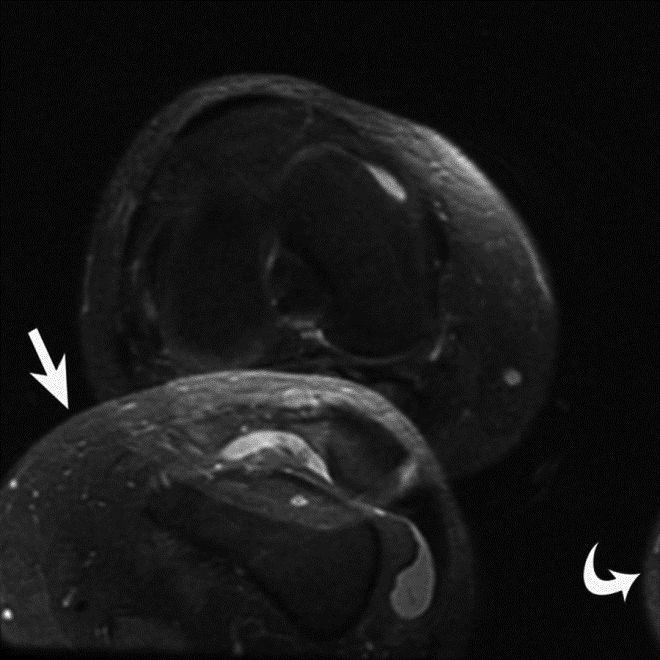

Repetitive, periodic motion can also occur due to cardiac activity or vascular pulsation and result in ghost images propagating along the phase-encoding direction (Peh, 2001). Pulsatile motion amplitude and speed will determine the brightness of this artifact (Wood, 1985). Cardiac or respiratory gating, as well as use of short acquisition times, may be used to minimize the effects of this periodic motion artifact; however, these artifacts are more problematic in cardiac and abdominal MR imaging than in musculoskeletal MR imaging (Singh, 2014). Pulsation artifact from the popliteal artery is a common manifestation of this artifact in musculoskeletal imaging, and may result in obscuration of the menisci (Figure 16).

Pulsation Artifact. Axial T2-weighted fat-saturated MR image of the pelvis demonstrates femoral artery pulsation resulting in ghost images (arrowheads) obscuring the anterior labra and simulating femoral head lesions bilaterally.